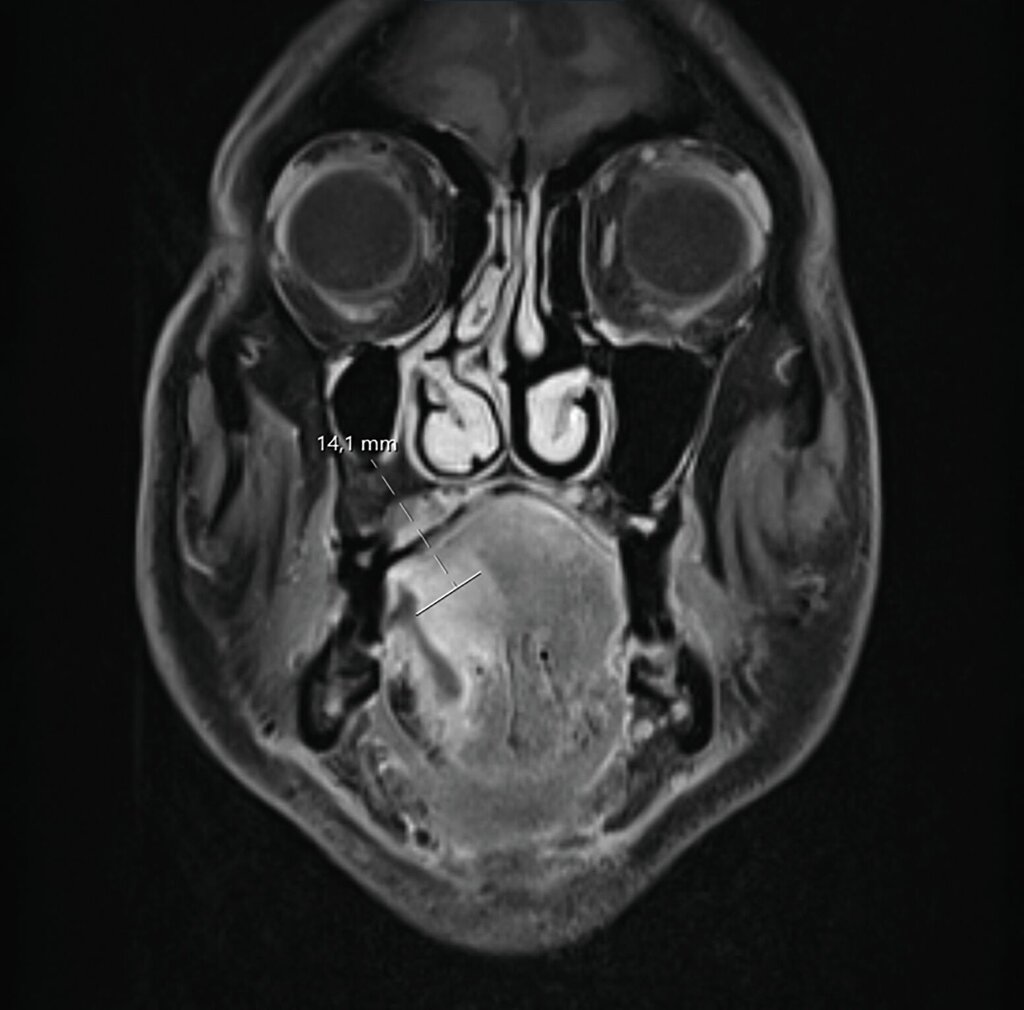

Ein Jahr später, im Februar 2025, stellte sich der Patient nach frustraner alternativmedizinischer Therapie erneut in der Universitätsklinik vor. Klinisch bestand nun eine deutliche Größenzunahme mit Annäherung an die Mittellinie (Abbildung 2). Die durchgeführte Bildgebung mittels MRT war aufgrund großer Ausleuchtungsartefakte der Zahnprothetik nur teilweise verwertbar. Allerdings zeigte sich der beschriebene Befund in T1-Richtung mit einer Tumordicke von circa 10 mm und einer Infiltrationstiefe von 5 mm (Abbildung 3).